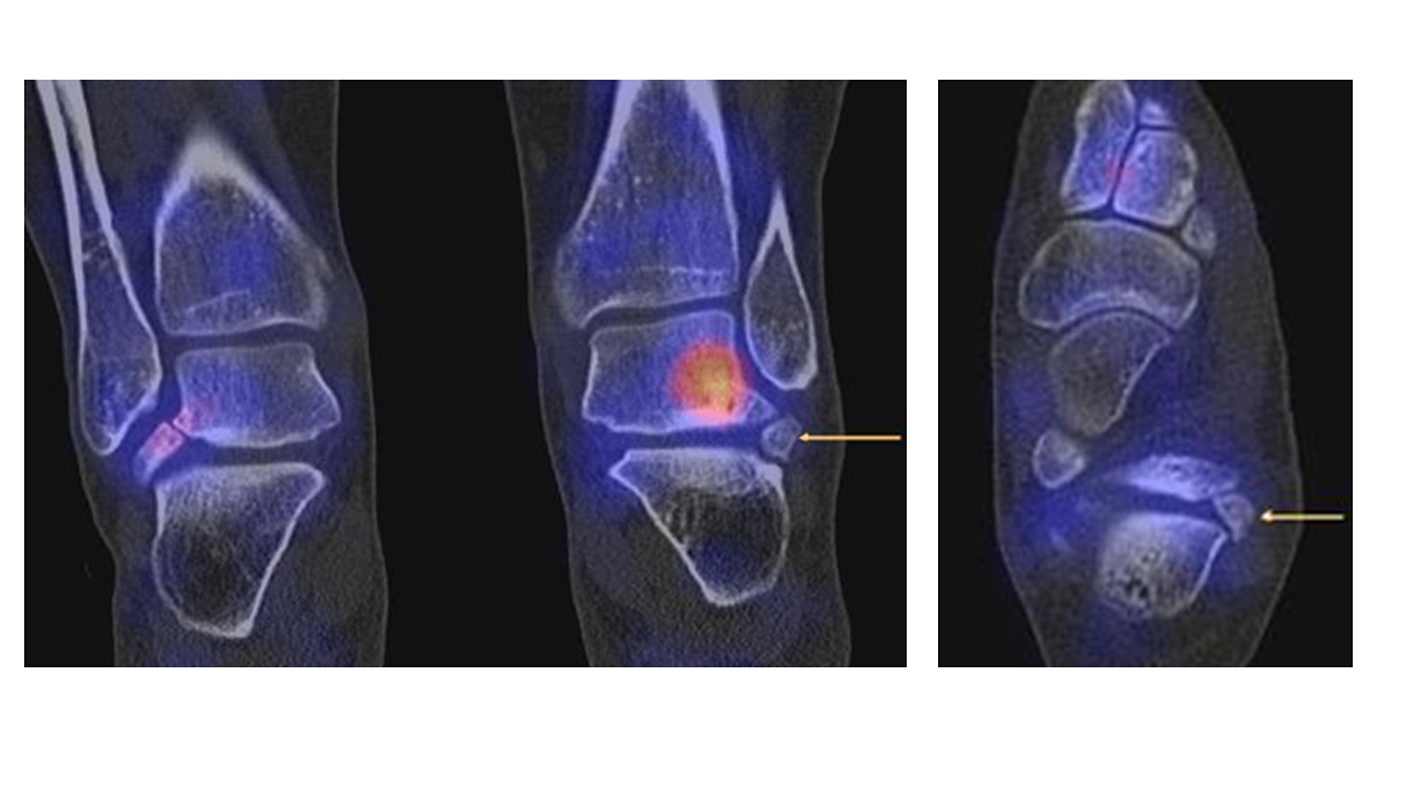

Abbildung 2.1.

Bildbeispiele symptomatische OCL

Zum Lesen der Bildbeschreibung und zur Vollansicht bitte das Bild anklicken. Bild: H. C. Rischke

Abbildung 2.2.

Bilder eines Patienten mit Z. n. mehrfachen Sprunggelenksdistorsionen in der Vergangenheit, besonders heftige Distorsion des linken Sprunggelenkes 5 Wochen vor der Untersuchung. Die SPECT/CT zeigt eine instabile osteochondrale Läsion mit deutlicher Aktivierung.

Abbildung 2.3.

Klärung bei Schmerzen im rechten OSG bei OCL an der medialen Talusschulter. Z. n. OSG-Distorsion vor 2 Jahren und Z. n. OSG-Fraktur / Syndesomosenruptur. Ausgedehnte OCL, hier jedoch kein erhöhter Knochenmetabolismus; lediglich Nachweis einer Stressreaktion im Bereich der Synchondrose eines Os trigonum als Schmerzursache.